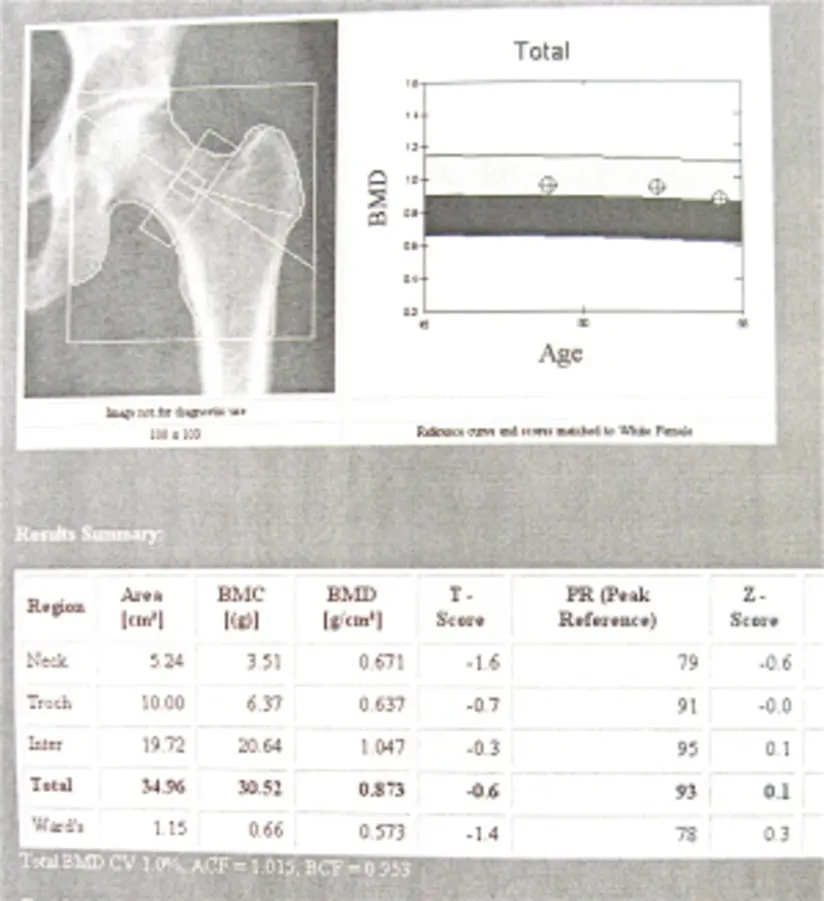

后来,您将获得Dexa结果,可能在与您的医生进行后续访问。你的臀部和脊柱的照片,很多数字,以及与您的年龄/性别的其他人相比,展示了你的骨密度的图表。

你将讨论的主要事情是你的t分。这是一个比较你的骨头到同性健康的年轻成年人,然后给你一个分数。零是健康的年轻成人分数。对于绝经后妇女,在-1之上的任何内容被认为是正常的。从-1.0到-2.5,你有骨质纲的核心。低于-2.5,你有骨质疏松症。

这是一种你可以和你的医生一起检查的图表。你的每一次扫描都有单独的一页:臀部、脊柱和手腕,如果你的手腕做了检查的话。